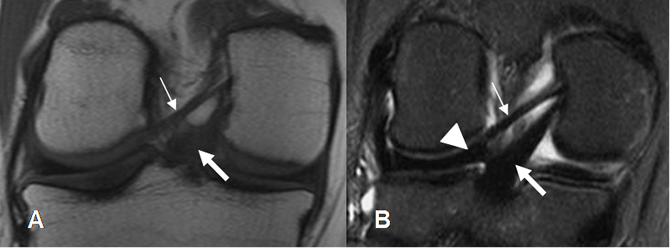

El LCP también se aprecia como una banda hipointensa en todas las secuencias. (2). (Fig 17). El ángulo entre los ejes de la inserción tibial y femoral, normalmente mide 123º. (11).

Este ligamento está rodeado por los ligamentos meniscofemorales que se originan del cóndilo femoral interno y se insertan en el menisco externo. Son el anterior o de Humphrey y el posterior o de Wrisberg. Estas estructuras no deben confundirse con cuerpos libres intra-articulares. (2). (Fig 18 y 19).

Fig 17. LCP normal.

A: RM sagital en T1 y B: RM sagital en T2. Ligamento normal, hipointenso en todas las secuencias.

Fig 18. Ligamentos meniscofemorales.

A y B: RM sagital en T1. Ligamento meniscofemoral anterior (Flecha delgada) y posterior (Flecha gruesa).

Fig 19. Ligamentos meniscofemorales normales.

A: RM coronal en T1 y B: RM coronal en STIR. Ligamento menisco femoral posterior (Flecha delgada), en relación con el LCP (Flecha gruesa). Menisco externo (Punta de flecha).